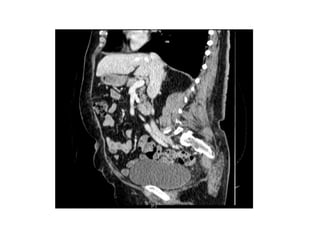

TAC TAP Septiembre

2016

Lesión 3ª porción

Duodeno 2-3cm

compatible con GIST.

Diseminación (-)

Imágenes:

• TAC:

– Delimita las grandes masas

exofíticas.

– Compromiso Local o distancia

– Guía Biopsia de tejido

TAC

• GIST Menor Tamaño

– Bien circunscritas,

homogéneas,

• GIST Mayor Tamaño:

– Masas Heterogéneas con

necrosis o hemorragia

central, Bordes Irregulares y

Crecimiento Extraluminal